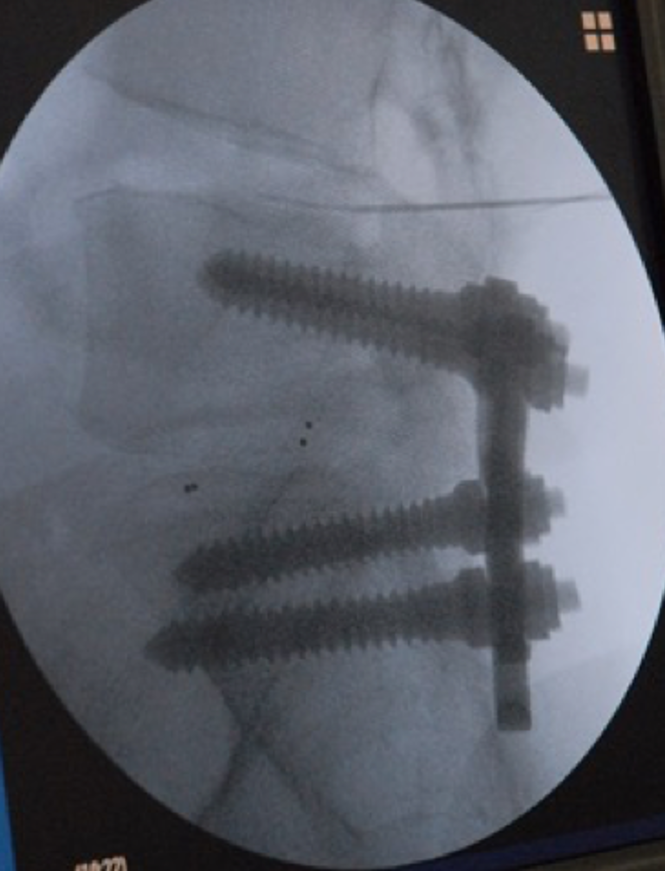

また、手術療法を行った場合は、症状のある部位を医療用ねじで固定してしまうため、時間が経つと固定した隣の部位に同じような変性疾患が生じてしまう可能性があります。